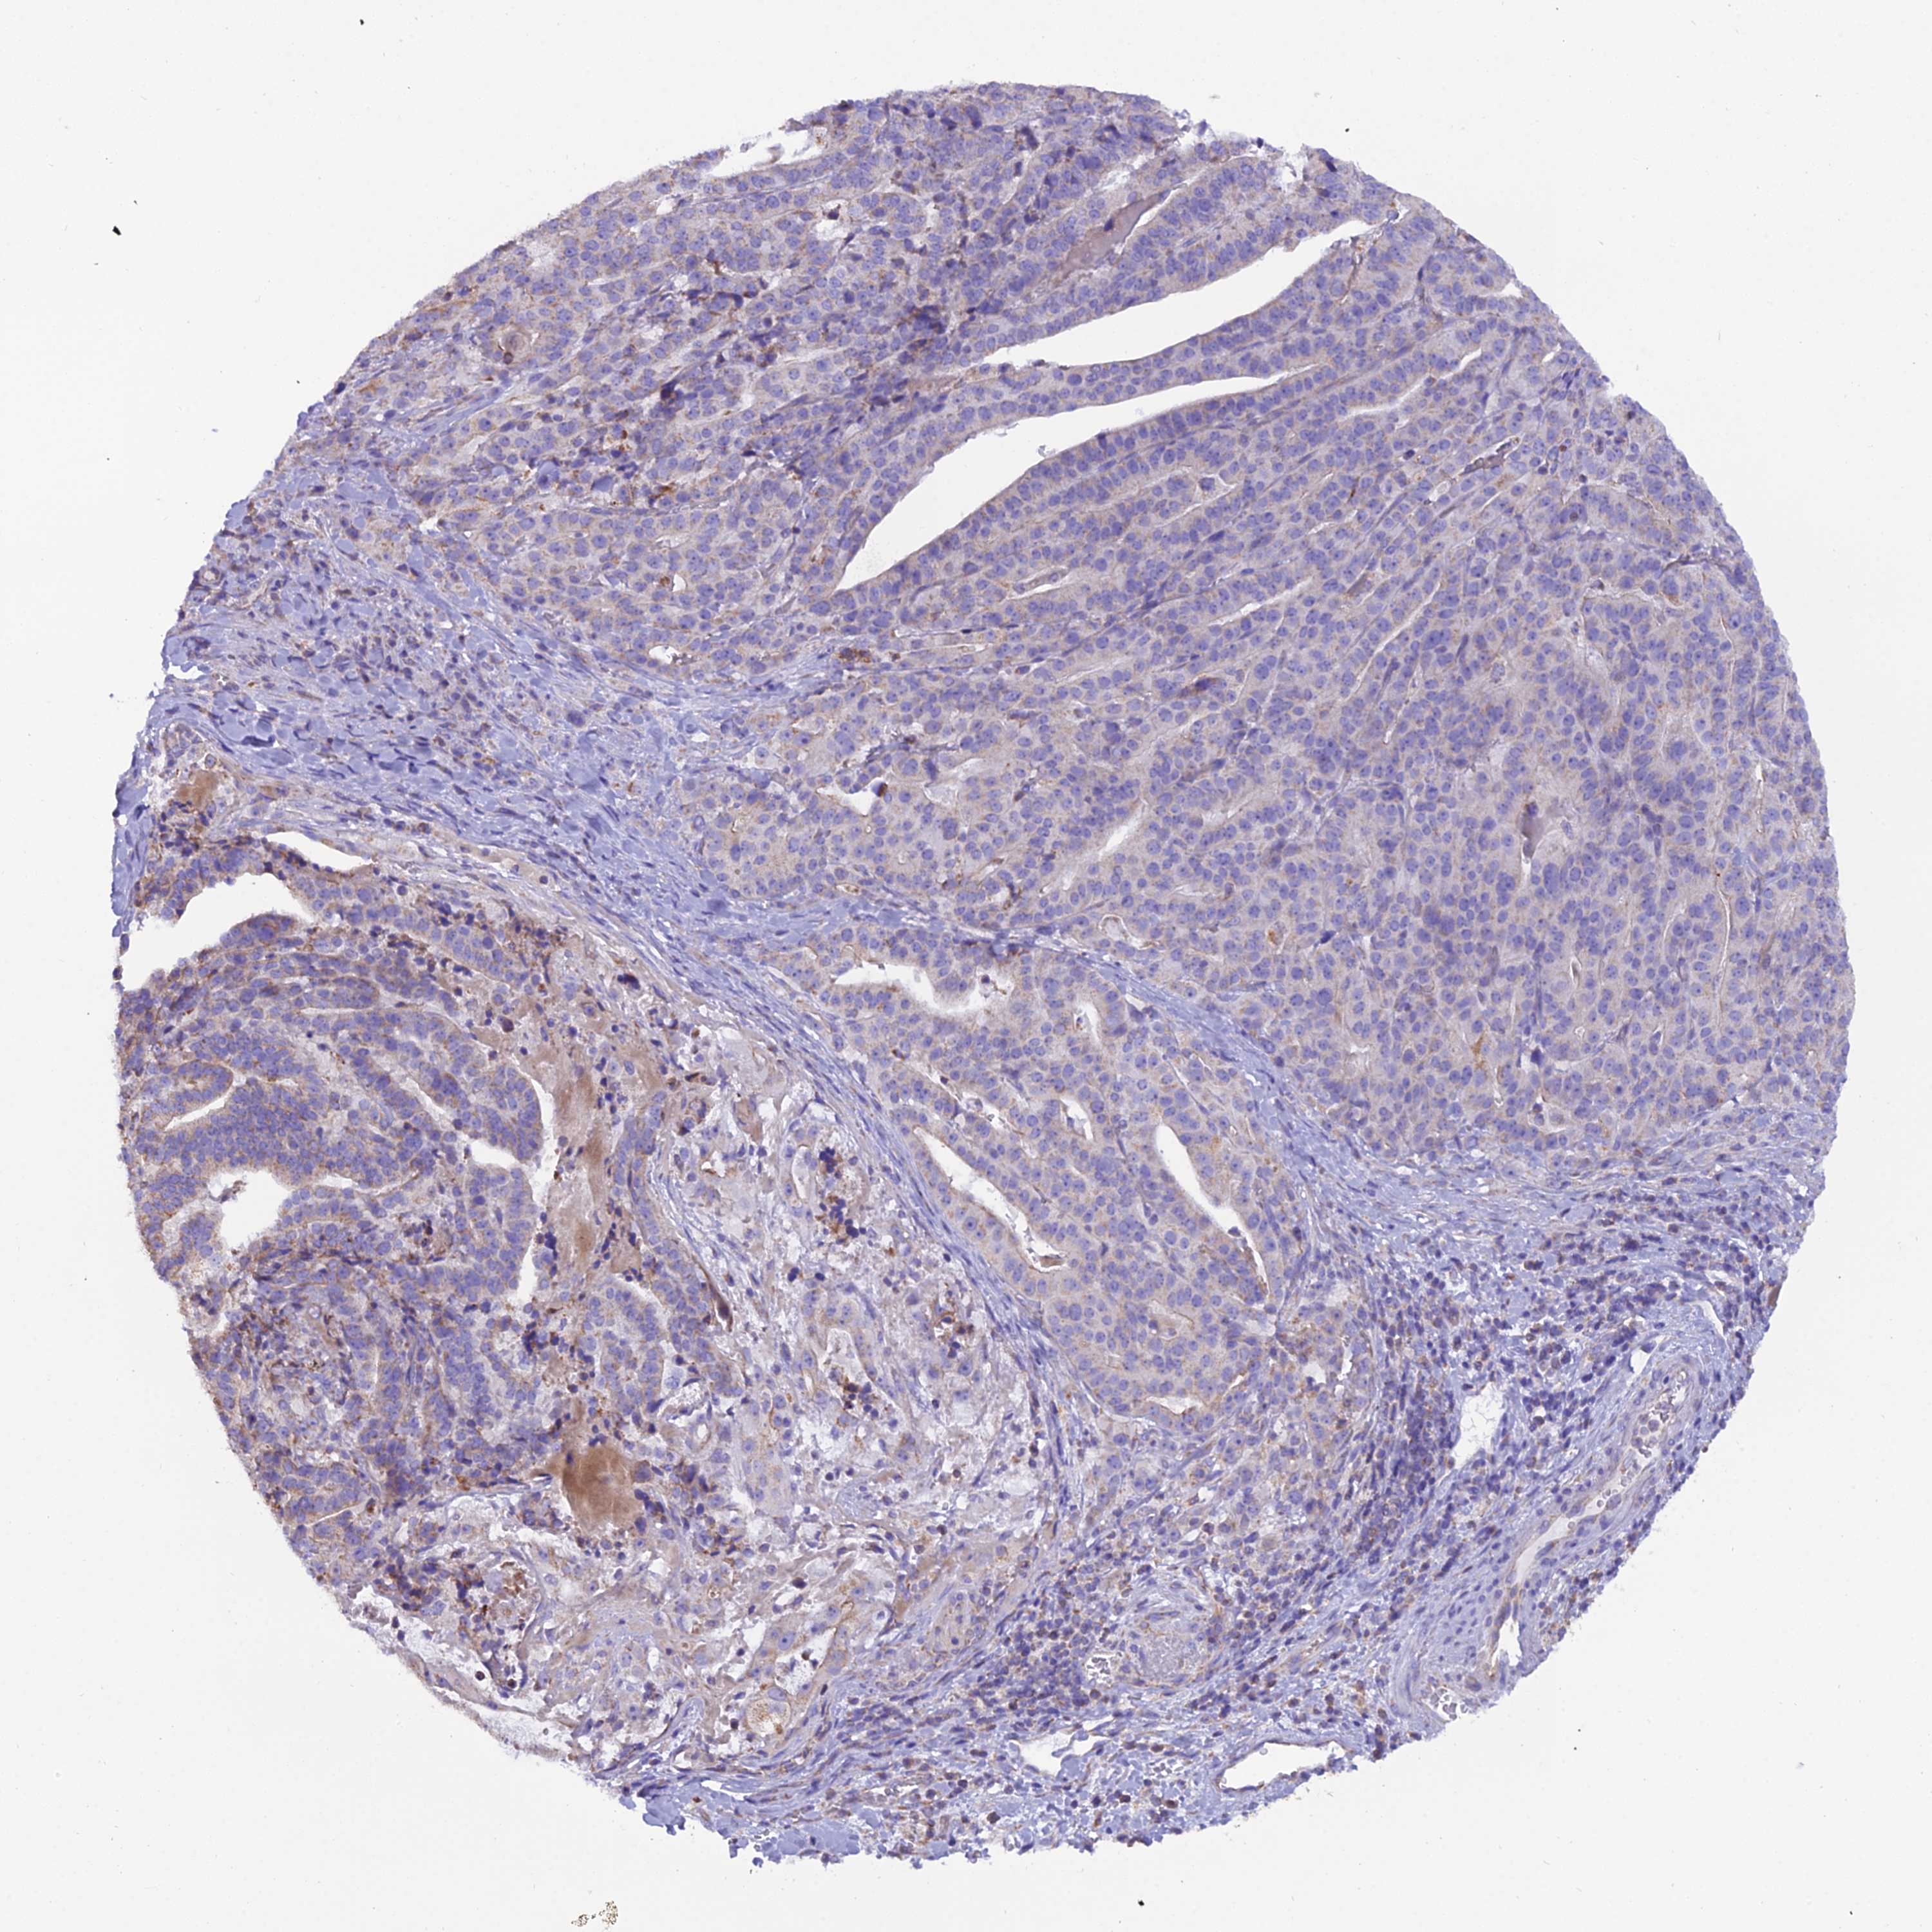

STOMACH CANCER - Protein expressioni

A mouse-over function shows sample information and annotation data. Click on an image to view it in a full screen mode. Samples can be filtered based on level of antibody staining by selecting one or several of the following categories: high, medium, low and not detected. The assay and annotation is described here.

Note that samples used for immunohistochemistry by the Human Protein Atlas do not correspond to samples in the TCGA dataset.

Antibody stainingi

Antibody staining in the annotated cell types in the current human tissue is reported as not detected, low, medium, or high, based on conventional immunohistochemistry profiling in selected tissues. This score is based on the combination of the staining intensity and fraction of stained cells.

Each image is clickable and will lead to virtual microscopy that enables deeper exploration of all samples and also displays staining intensity scores, fraction scores and subcellular localization as well as patient and tissue information for each sample.

Antibody HPA044620

Antibody HPA058621

Staining

High

Medium

Low

Not detected

Intensity

Strong

Moderate

Weak

Negative

Quantity

>75%

75%-25%

<25%

None

Location

Nuclear

Cytoplasmic/membranous

Cytoplasmic/membranous,nuclear

Adenocarcinoma, NOS

Adenocarcinoma, High grade